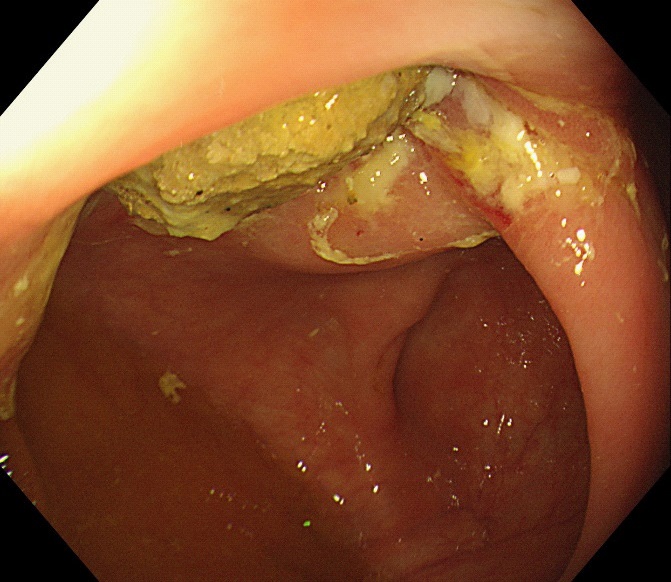

Figure 1: The computed tomography scan of abdomen showed about 20 mm X 20 mm circular high density shadow in right colon.

The computed tomography scan of abdomen showed about 20 mm X 20 mm circular high density shadow in right colon, which can be observed in colonic lumen but protruding out of the lumen. Colonoscopy (Figure 3) was also performed and the fecal impaction was identified in the cecal diverticulum above the ileocecal valve. The mucosa surrounding the diverticulum was hyperemic and edema. Than the fecalith was removed successfully with a foreign forceps under colonoscopy. The internal mucosa of the diverticulum was hyperemia, and no perforation was observed (Figure 4). The patient’s abdominal pain were relieved after endoscopic treatment. To prevent recurrence of the disease, surgical removal of the diverticulum was recommended but the patient was hesitant. There was no recurrence of abdominal pain and fecal impaction during 10 months follow-up.